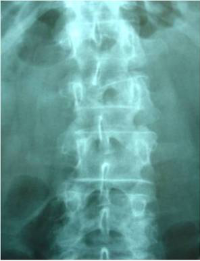

Caso clínico con estabilización percutánea de fractura vertebral inestable.